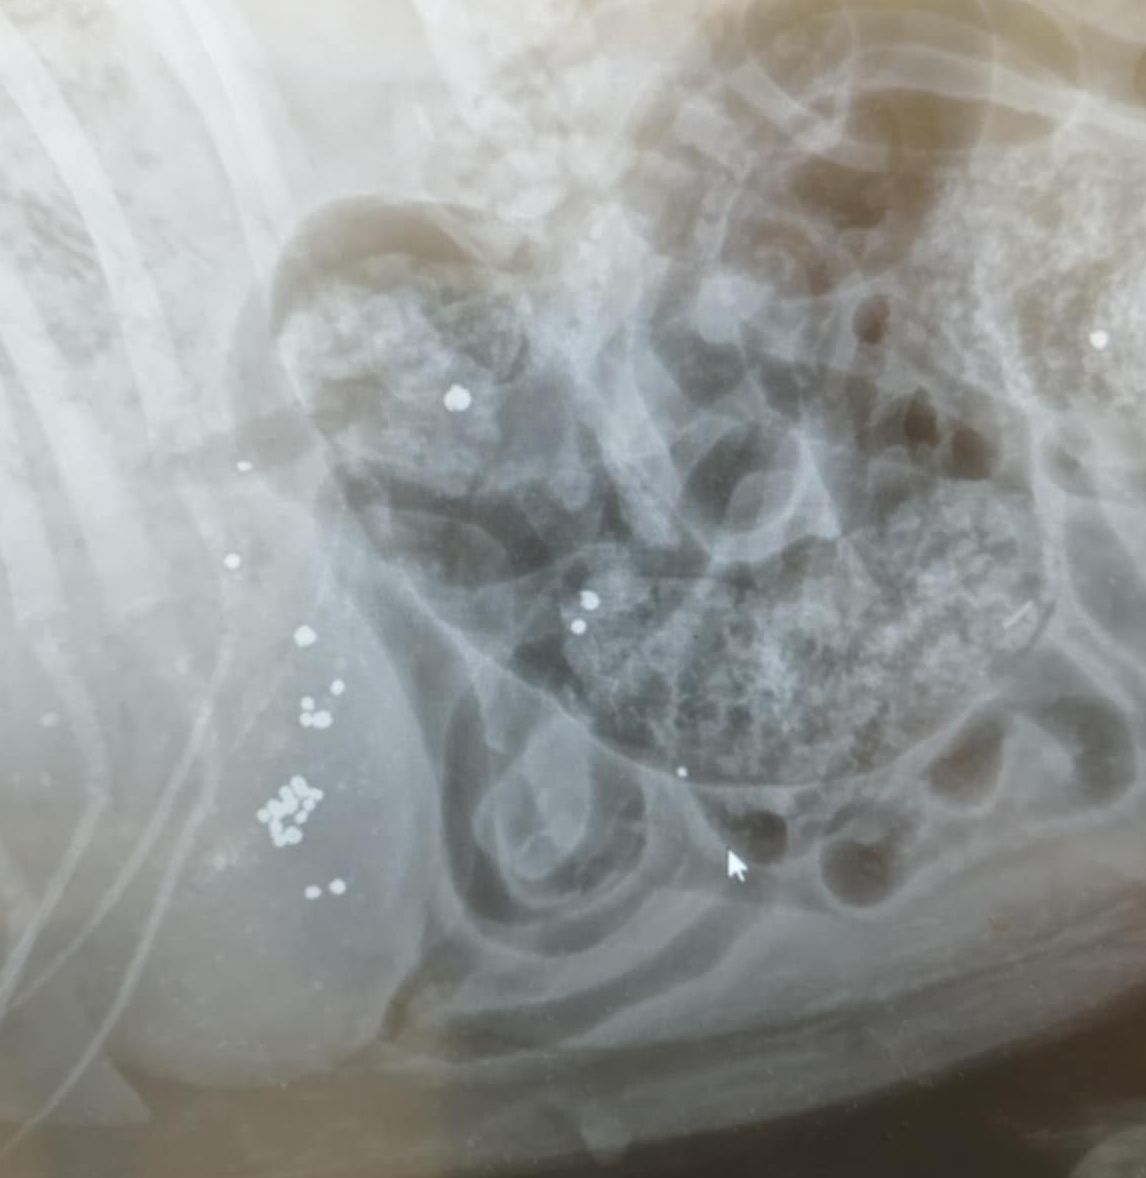

Τελικά οι ακτινογραφίες έδειξαν τι έχει συμβεί. Ο σκύλος είναι πυροβολημένο. Δεκάδες σκάγια εντοπίστηκαν στο σώμα του, στην σπονδυλική στήλη με αποτέλεσμα το ζώο να μην μπορεί όχι μόνο να κινηθεί αλλά και να αφοδεύσει με αποτέλεσμα στο έντερο να έχουν συσσωρευθεί κόπρανα.

Η Ευτυχία Πουρνάρα με αφορμή το περιστατικό επισήμανε τα εξής στις 3 Ιανουαρίου: «ΦΙΛΟΙ ΜΟΥ ΒΟΗΘΗΣΤΕ ΑΥΤΟ ΤΟ ΠΛΑΣΜΑ ΝΑ ΓΙΝΕΙ ΚΑΛΑ ΓΙΑΤΙ ΕΝΩ ΜΟΥ ΕΙΠΑΝ ΠΡΕΠΕΙ ΝΑ ΤΟ ΧΤΥΠΗΣΕ ΑΥΤΟΚΙΝΗΤΟ  ΣΥΓΚΛΟΝΙΣΤΙΚΑ ΟΤΑΝ ΟΙ ΑΚΤΙΝΟΓΡΑΦΙΕΣ ΔΕΙΞΑΝ ΟΤΙ ΤΟ ΚΟΡΜΑΚΙ ΤΟΥ ΣΚΥΛΑΚΟΥ ΕΙΤΑΝ ΓΕΜΑΤΟ ΣΚΑΓΙΑ ΔΙΑΣΠΟΡΑΣ ΕΝΑ ΤΟ ΒΡΕΙΚΕ ΣΤΗΝ ΣΠΟΝΔΥΛΙΚΗ ΣΤΥΛΗ Ο ΓΙΑΤΡΟΣ ΜΟΥ ΚΥΡΙΟΣ ΚΑΡΑΜΗΤΡΟΣ ΜΟΥ ΕΔΩΣΕ ΑΓΩΓΗ  ΤΟ ΖΩΟ ΔΕΝ ΜΠΟΡΟΥΣΕ ΝΑ ΑΦΟΔΕΥΣΗ ΚΑΙ ΠΡΙΣΤΗΚΕ ΚΑΝΟΥΜΕ ΑΓΩΝΑ ΝΑ ΤΟ ΒΟΗΘΗΣΟΥΜΕ ΤΟ ΚΑΛΟ ΕΙΝΑΙ ΟΤΙ ΑΙΣΘΑΝΕΤΑΙ ΤΑ ΠΟΔΑΡΑΚΙΑ ΤΟΥ ΘΑ ΣΑΣ ΠΩ ΝΕΟΤΕΡΑ ΤΟ ΚΑΘΑΡΜΑ ΠΟΥ ΤΟ ΠΥΡΟΒΟΛΗΣΕ  ΕΥΧΩΜΕ ΑΥΤΟ ΠΟΥ ΕΚΑΝΕ ΝΑ ΤΟ ΒΡΕΙ ΜΠΡΟΣΤΑ ΤΟΥ ΜΗΝ ΞΕΧΝΑΤΕ ΒΟΗΘΗΣΤΕ  ΕΧΩ ΑΓΩΝΑ ΜΠΡΟΣΤΑ ΜΟΥ ΓΙΑ ΝΑ ΣΩΘΕΙ ΣΤΕΙΛΤΕ ΜΗΝΝΥΜΑ ΣΤΟ ΜΕΣΣΕΝΤΖΕΡ  ΕΥΧΑΡΙΣΤΩ ΠΟΛΥ ΤΗΛ 6946348888 ΚΙΛΚΙΣ».